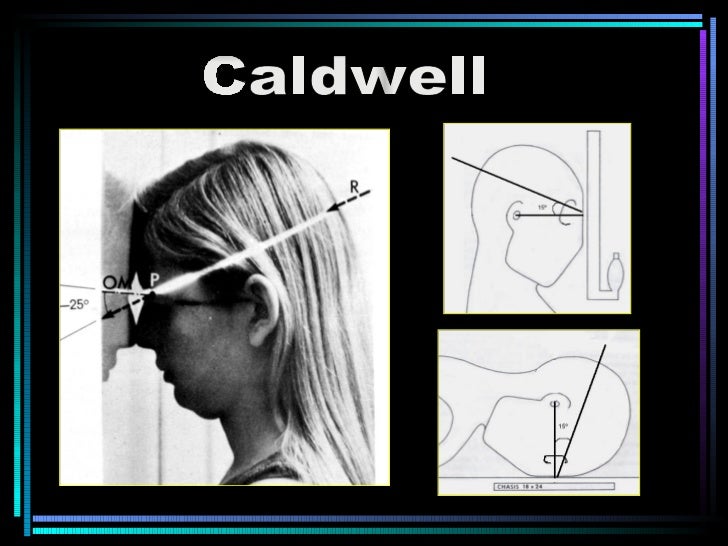

Download scientific diagram | Proyección de Waters: aumento de densidad de partes blandas de los senos maxilares (estrella) y presencia de masa en la faringe (flecha). from publication: Pólipo.. Citation, DOI, disclosures and article data. The Caldwell view is a caudally angled radiograph, with its posteroanterior projection allowing for minimal radiation to the orbits. This view may be used in imaging of the skull or facial bones depending on the clinical indications.

Proyección de Caldwell Wikiwand

Incidencias de CADWELL y WATERS NeuroMedicine uDocz

Descarga RX – Posiciones Radiológicas: https://play.google.com/store/apps/details?id=com.Tarter.RXPosicionesRadiolgicas&pcampaignid=web_sharehttps://apps.app.. Study with Quizlet and memorize flashcards containing terms like Proyección de Caldwell también llamada., Proyección de Waters también llamada., ¿Qué estructuras se aprecian mejor con la proyección de Caldwell? and more.